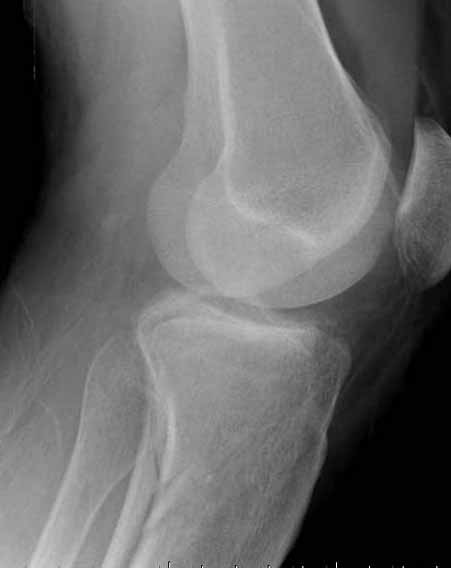

Для изолированных переломов медиального тибиал плато, фиксацию можно провести “медиальной пластиной”. Некоторые компании, например Smith & Nephew делают медиальные и медиально-задние пластины, но они мягкие, и легко можно создать нужный контур. Жесткость создается за счет фиксации жесткими пластинами, например экстра артикулярной пластиной для дистального плеча от Synthes. Медиальный доступ тоже не из легких, надо работать между pes and medial gastroc.

Частая ошибка, когда фиксацию двух колонного перелома проводят одиночной пластиной, т.е с одной стороны, и такая фиксация не удерживает, происходит вторичноое смещение. Необходимо нейтрализовать второй пластиной или дополнительным наружным фиксатором.

Если у вас, кроме пластины, нет другого альтернативного варианта, тогда, учитывая мягкотканые проблемы с наружной стороны, я бы рекомендовал операцию делать в два этапа. Преимущества, сперва репозиция и фиксация перелома с медиальной стороны, а затем, после улучшения состояния мягких тканей, зафиксировать с латеральной стороны. Современные пластины имеют латеральный Jig для перкутанных мини доступов.

В приложении этапы фиксации Both Column Fx и пластиной Synthes для плеча при переломе медиального мыщелка.